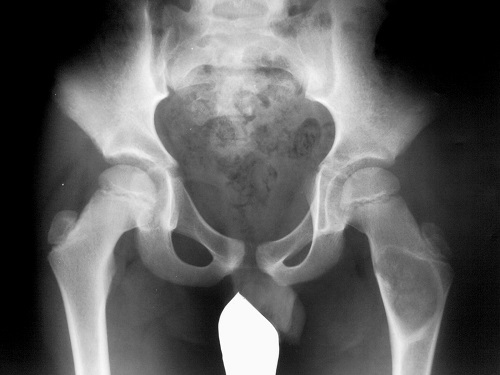

Фиброзная дисплазия, или фиброзно-кистозная болезнь кости относится к системному заболеванию скелета, которое выражается в нарушении развития костной ткани, а именно, в ее замещении на ткань фиброзную, что приводит к деформации кости. Этот вид дисплазии, так же как и другие ее виды: фиброзно-мышечная, эктодермальная, цервикальная и прочие, не является истинно опухолевым, однако он стоит совсем рядом с новообразованиями.

Фиброзная дисплазия может поразить любую кость. И диффузные, и очаговые поражения располагаются в диафизах и метафизах, чаще всего в длинных трубчатых костях рук и ног. Наиболее часто этой болезни подвергаются большеберцовая, бедренная, лучевая и плечевая кости, также нередко страдают ребра.

Очаги поражения могут возникать как на совсем небольших участках костей, так и на значительных. В самом начале развития заболевания пораженные участки скелета способны сохранять свои первоначальные и форму, и размеры. Со временем начинают появляться очаги «вздутия», костная ткань начинает деформироваться: удлиняться или, наоборот, укорачиваться.

На распиле кости определяются белые, с красноватыми вкраплениями очаги, которые обычно имеют округлую или удлиненную форму, иногда сливающиеся между собой. При этом канал костного мозга расширен и заполнен новообразованными тканями.